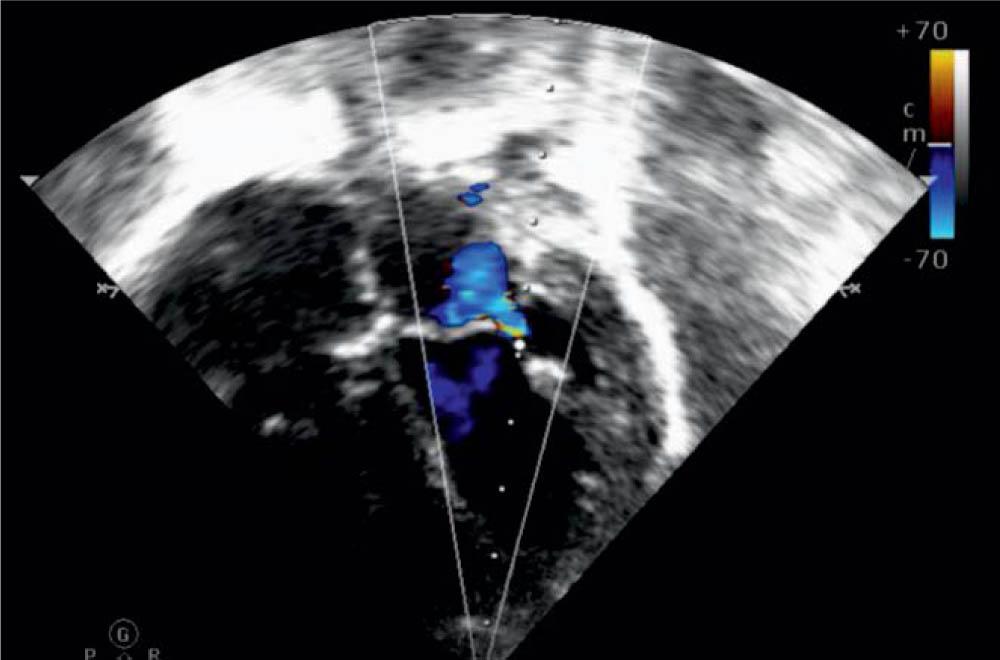

The electrocardiogram was normal. Repeated transthoracic echocardiography confirmed the moderate-severe systolic dysfunction (LVEF = 30–40%), the thin layer of pericardial effusion, a right pleural effusion of about 16 mm, Figure 1, mild mitral regurgitation, Figure 2, initial normal coronary artery diameter, but in evolution, in the fifth day dilated coronary arteries were noticed - the left main coronary artery measured 3.4 mm (Z-score = 2.8), the left anterior descending coronary artery measured 2.5 mm (Z-score = 2.6), and the right coronary artery was of normal size 2 mm (Z-score = 0.6) (Figure 3).

Figure 3

Left main coronary artery in the proximal segment showing a dilation of 3.4 mm (z score 2.8).